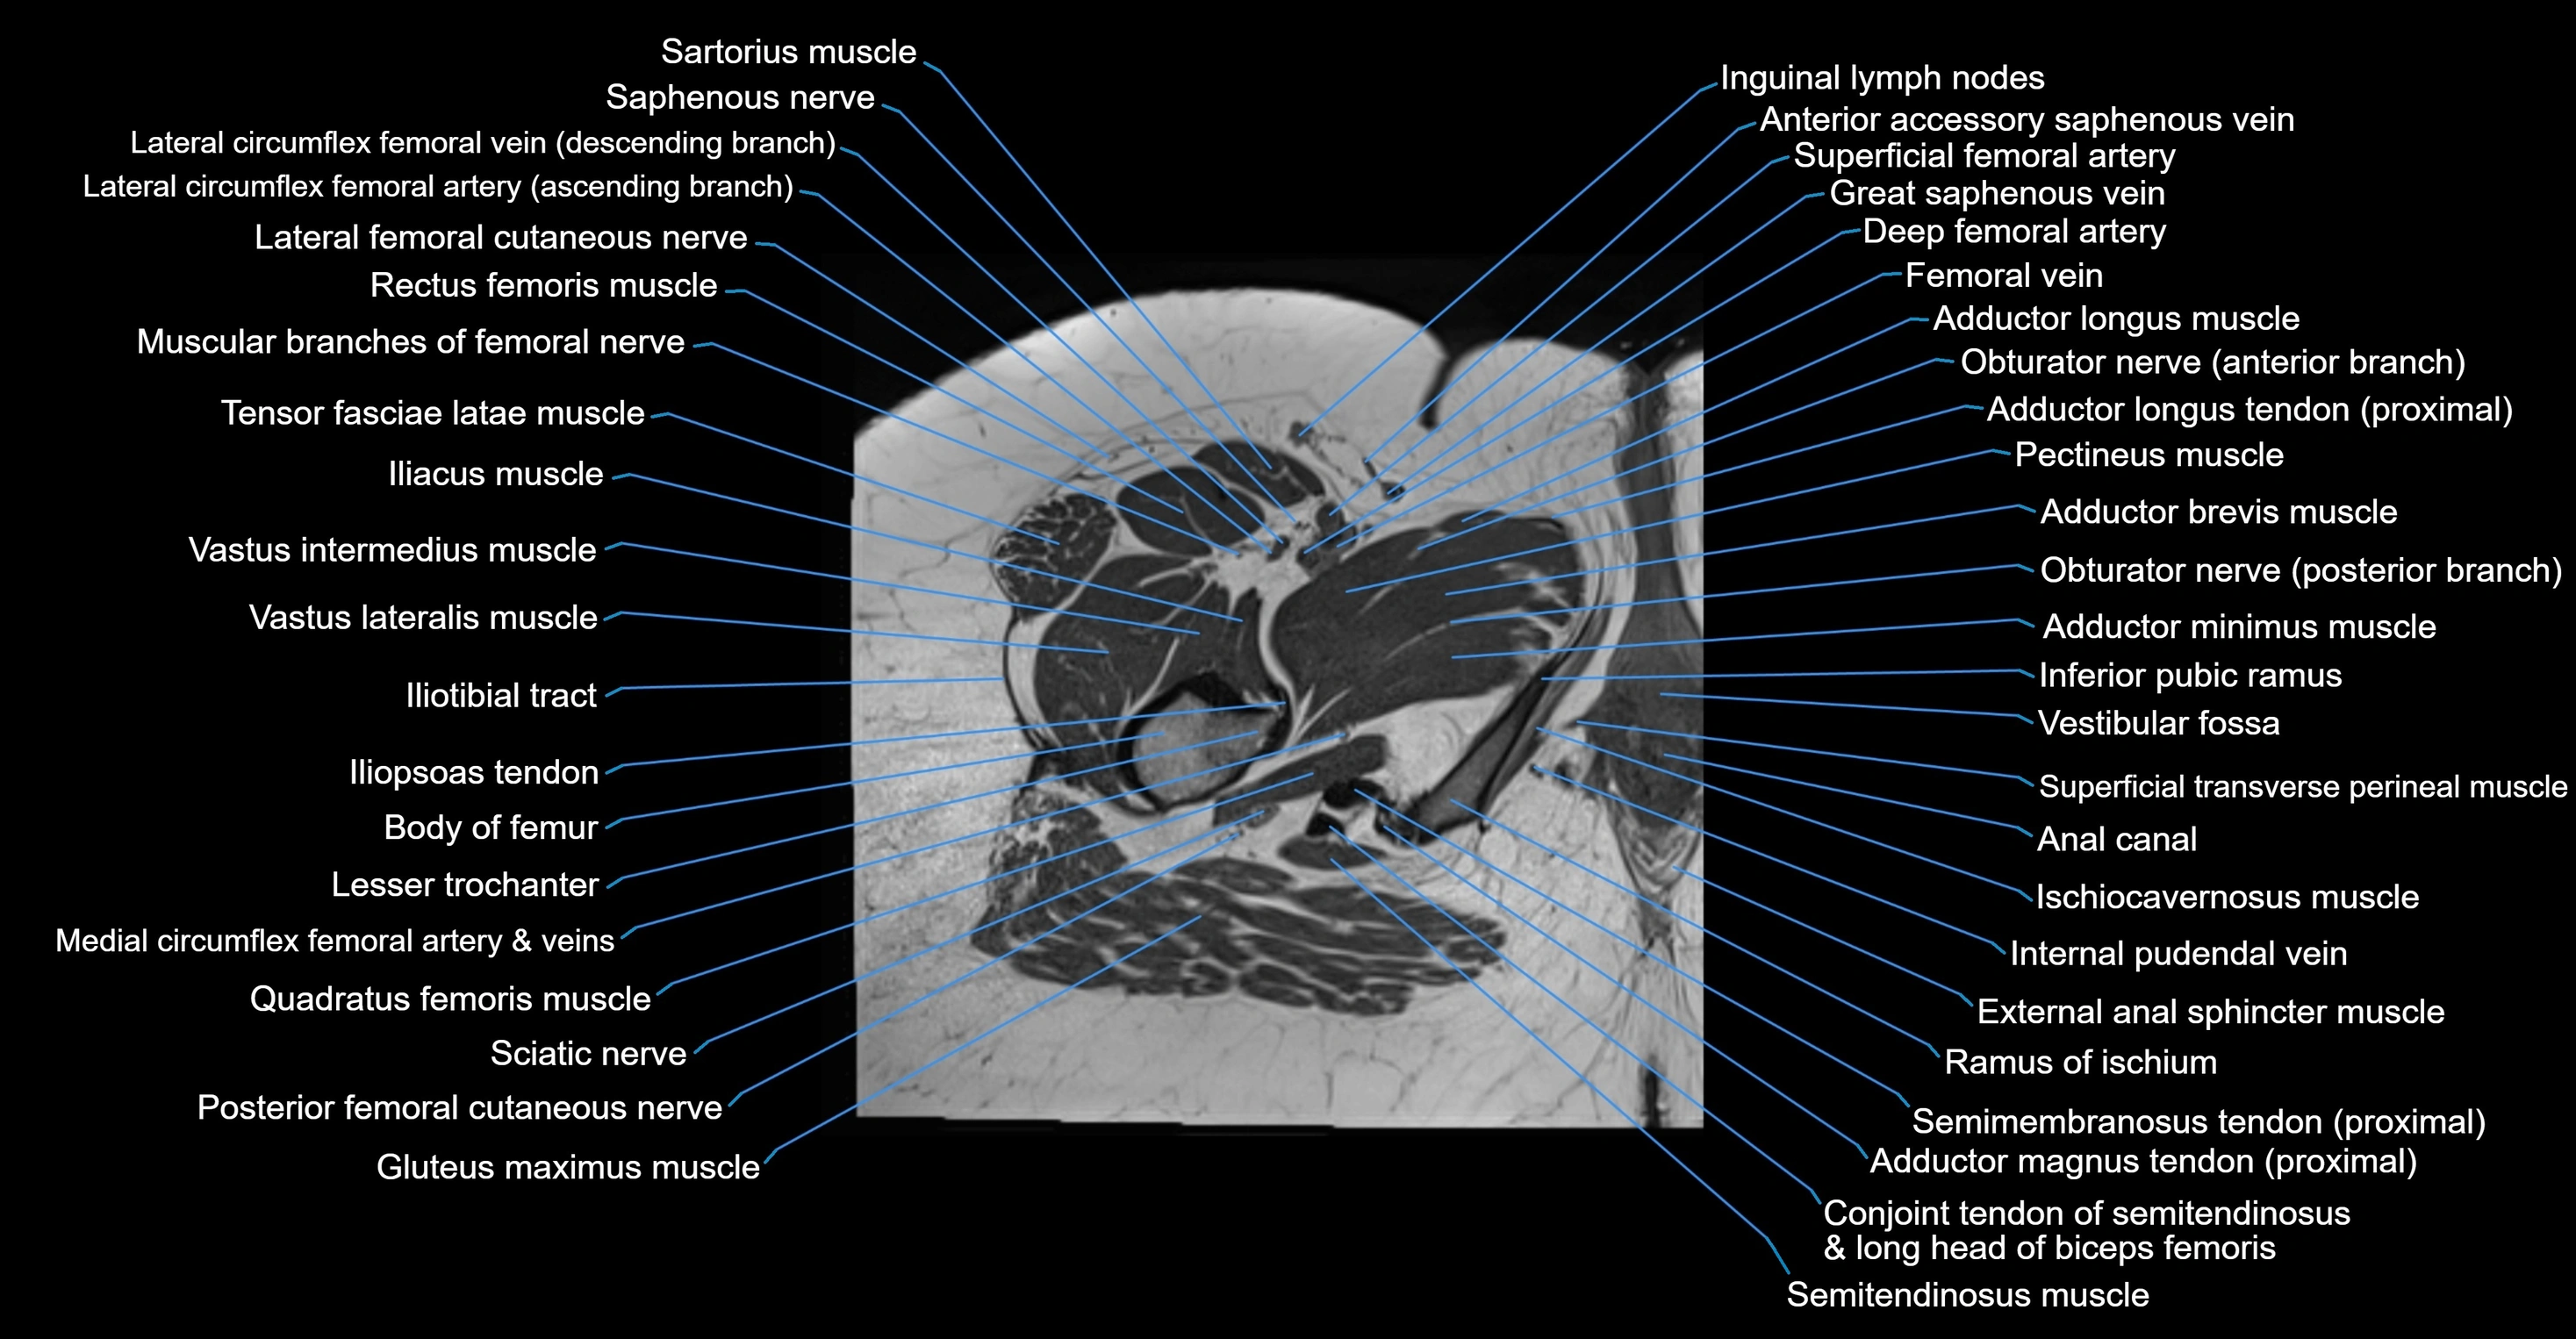

- Adductor brevis muscle

- Adductor longus muscle

- Adductor minimus muscle

- Anal canal

- Conjoint tendon of biceps femoris & semitendinosus

- Femoral artery

- Femoral nerve

- Femoral vein

- Gracilis muscle

- Iliopsoas tendon

- Iliotibial tract

- Inferior pubic ramus

- Inguinal lymph nodes

- Ischiocavernosus muscle (Female)

- Ischiocavernosus muscle (Male)

- Lateral femoral cutaneous nerve

- Lesser trochanter

- Muscular branches of femoral nerve

- Pectineus muscle

- Posterior femoral cutaneous nerve

- Ramus of ischium

- Saphenous nerve

- Sartorius muscle

- Semimembranosus tendon (proximal)

- Superficial femoral artery

- Superficial transverse perineal muscle

- Tensor fasciae latae muscle

- Vastus intermedius muscle

- Vastus lateralis muscle

- Vestibular fossa